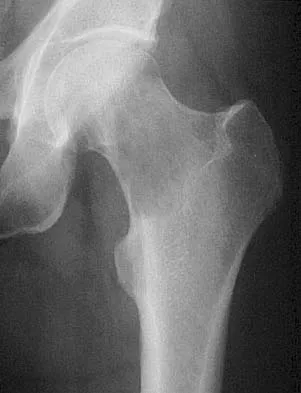

A 47-year-old woman has had a 1-month history of left hip and medial thigh pain that is exacerbated by sitting. Laboratory studies show a total protein level of 8.2 g/dL (normal 6.0 to 8.0) and an immunoglobulin G (IGG) level of 2,130 mg/dL (normal 562 to 1,835). A radiograph, CT scan, and biopsy specimen are shown in Figures 38a through 38c. What is the most likely diagnosis?

Explanation

The laboratory studies and histology are both consistent with myeloma. Infection should show white blood cells other than plasma cells on histology. Lymphoma would show lymphocytes, not plasma cells. The lack of bone formation on the imaging studies and the lack of osteoid on histology rule out osteosarcoma. The cells have too much cytoplasm and nuclear chromatin to be Ewing's sarcoma cells.